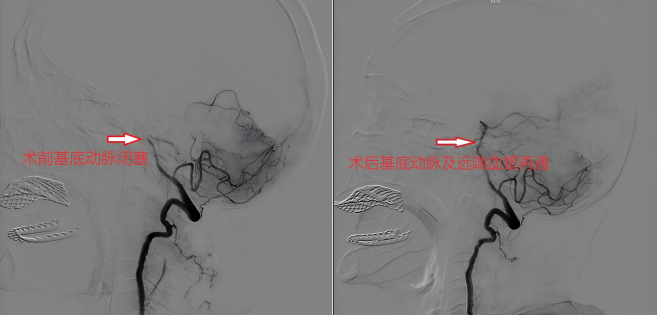

近年来,大竹县人民医院紧紧依托公立医院改革与高质量发展示范项目,大力发展神经介入微创技术,在提升医院综合技术实力方面取得了显著成绩。近日,我院神经内科就为一名87岁高龄重型脑梗死患者成功完成了急诊微创取栓术(不开颅,经右侧股动脉入路插管取栓),仅用40多分钟就成功开通患者的闭塞脑血管,成功挽救了患者的生命。

据悉,患者陈婆婆因突发左侧肢体完全瘫痪1小时被家属送至大竹县人民医院急诊科,急诊科立即启动“脑卒中绿色通道”,急诊抽血,急诊头颅CT提示颅内未见出血及梗死灶,急诊科以“脑梗死”收入神经内科。神经内科李朝晖主任团队立即详细询问患者病史并进行仔细的专科查体后诊断为脑梗死。高龄+脑梗死这一情况,对神经内科医疗团队来说无疑是一个不小的挑战,内科保守治疗很有可能效果不佳导致终身残疾甚至进一步加重死亡,静脉溶栓又担心会出现出血导致更严重的后果,于是经过团队积极讨论分析,神经内科医疗团队为患者提出了神经介入的治疗方案。在征求患者子女同意后,迅速为患者进行了“主动脉弓造影术+全脑血管造影术+基底动脉栓塞血栓抽吸术”,经过40多分钟的努力,成功取出血栓,开通患者闭塞血管。此次手术取得良好治疗效果,术后第二天患者便可下床行走,一个星期后顺利出院,患者和患者子女多次诚挚感谢神经内科的救命之恩。